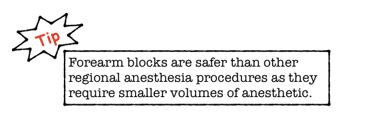

US guided nerve blocks in the forearm target the Radial, Median and Ulnar nerves. They are indicated for pain control in various hand injuries including lacerations, fractures, and deep soft tissue infections. Contraindications include an infection at the site of injection, allergy to anesthetic, risk for compartment syndrome, and the uncooperative patient. Emergency physicians who have had only one hour of training can anesthetize all 3 nerves in under 10 minutes.3 These blocks can be used individually, or in conjunction, to achieve either partial or total anesthesia of the hand.4-5 Using forearm blocks for hand anesthesia may actually reduce the risk of local anesthetic systemic toxicity when compared to extensive local injection.6 Below we describe the technique for ultrasound guided regional anesthesia of the hand.